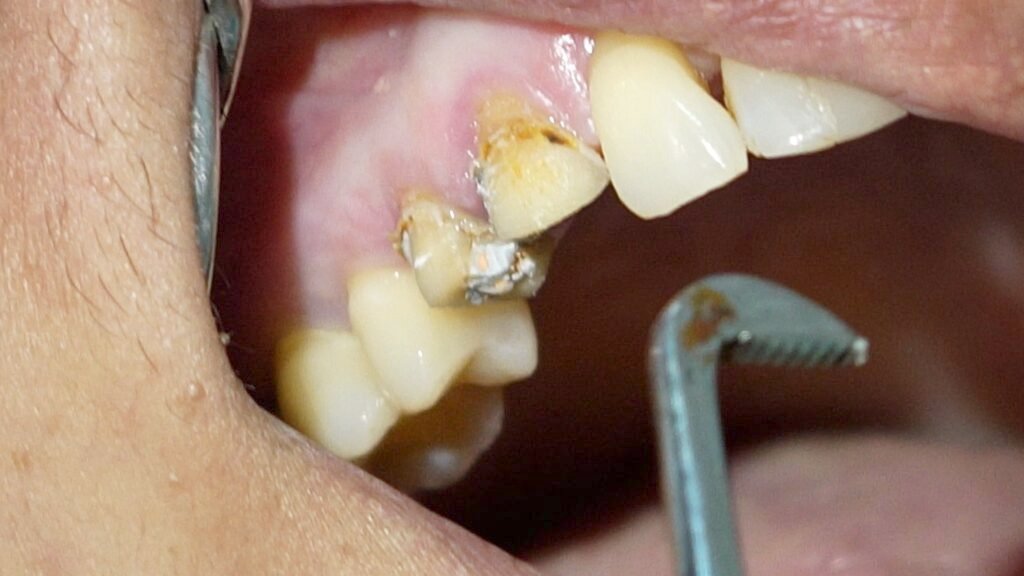

I explained the situation to the patient, noting that the tooth had been treated improperly and both the tooth and broken file would need to be removed. After removing the porcelain crown, I found that the restoration underneath was temporary and that dental caries were not properly cleaned out—an important first step before any root canal treatment

I then extracted the tooth, which showed overfilled canals, but unfortunately, the broken file did not come out with the tooth. A follow-up X-ray confirmed the file remained in the bone. Using a high-magnification microscope and special illumination, I performed a surgical procedure to carefully remove the broken file from the bone. The patient’s discomfort was resolved after a few days, and she recovered well.